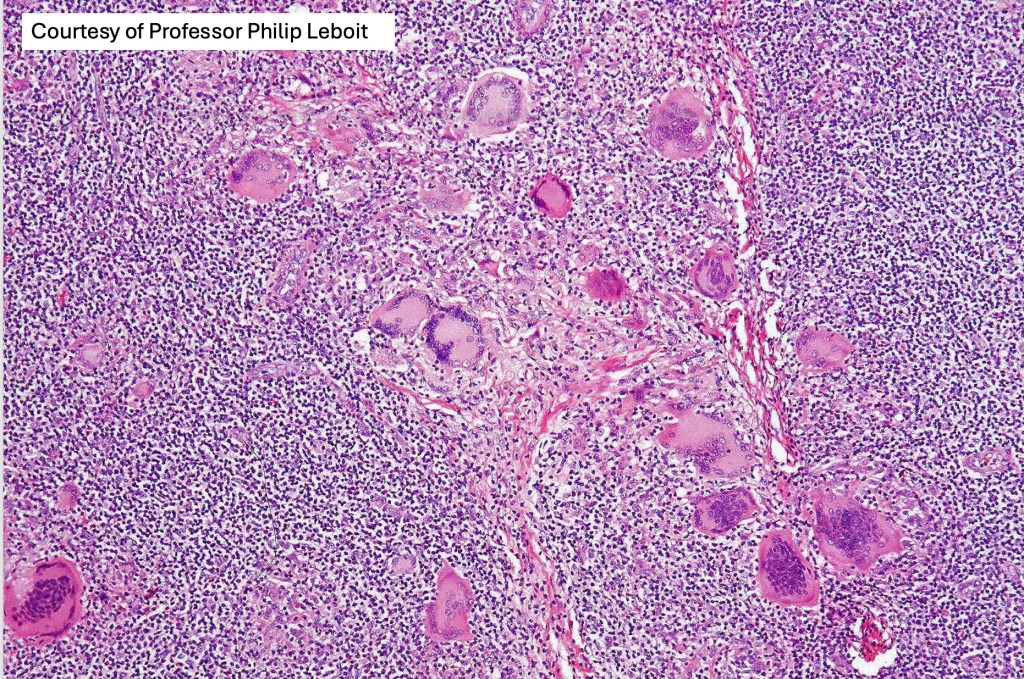

•Established lesions are readily recognizable & characterized by a dense infiltrate throughout the dermis &extending into subcutaneous fat

•Atypical, hyperchromatic lymphocytes, Sezary cells, histiocytes, plasma cells, eosinophils & characteristic multinucleate giant cells (innumerable nuclei resembling a shoal of fish)

•Lymphophagocytosis is generally marked

•Discrete granulomata often evident & in some cases may be the dominant feature obscuring the background lymphomatous infiltrate

Granulomatous mycosis fungoides by way of a comparison